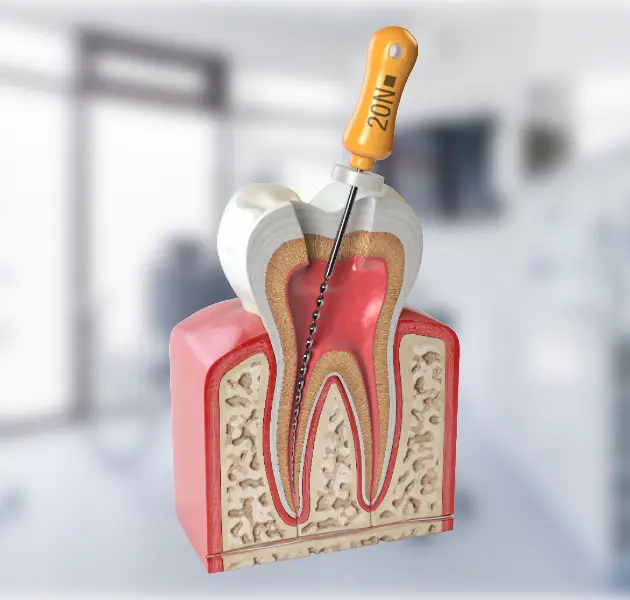

ENDODONZIA

La polpa dentale viene rimossa con strumenti endodontici che ripuliscono e sagomano adeguatamente i canali presenti all’interno delle radici del dente. Dopo aver rimosso ogni residuo di tessuto pulpare e disinfettato abbondantemente mediante l’irrigazione di specifici medicinali, si procede alla completa sigillatura tridimensionale degli spazi canalari attraverso l’uso di materiale termoplastico.